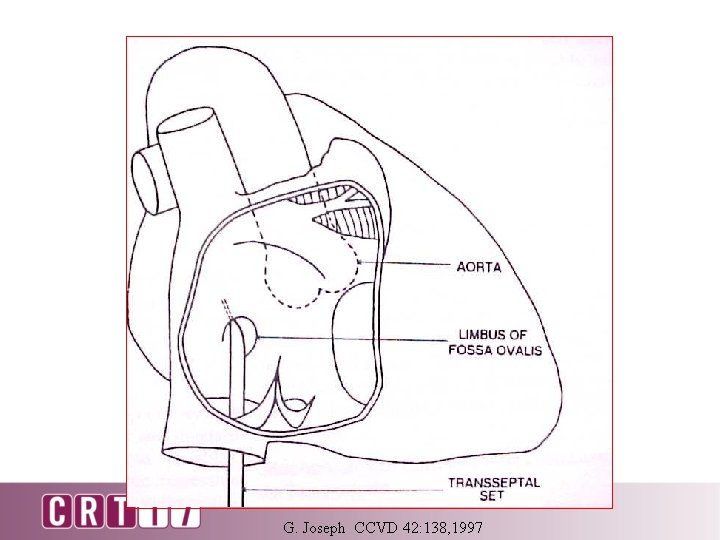

G. Joseph CCVD 42: 138, 1997